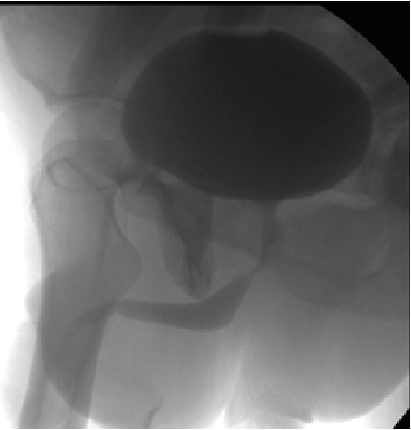

Retrograde urethrography is a very dynamic study, which must be taken into account when acquiring images, especially when sending still images, a common error is the leakage of contrast towards the skin (Figure 1) avoiding using a Foley catheter at the level of distal urethra to retain the contrast, however it can condition trauma [1]. Another common error is the ignorance of ideal projections for evaluation of the urethra (Figure 2), for example the Lauenstein projection, which is more useful for evaluating the hip. The imaging with a lack of contrast between the structures (Figure 3), which can be modified during and after the acquisition. It should be noted that on some occasions, in case of doubt, images will be taken from two different x-ray directions.

Figure 1: Contrast Drainage in Skin, Can Simulate Double Urethra or False Via